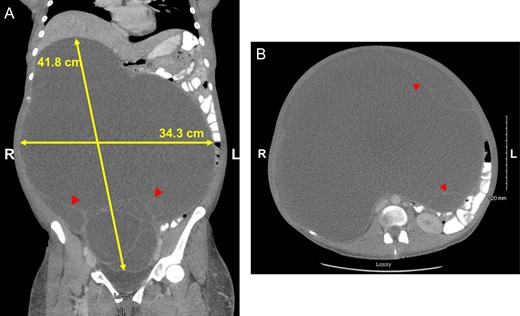

The patient was 168 cm tall and weighed 194 lb (88 kg). On physical exam, the most notable finding was a massively distended abdomen consistent in size with a 9-month gestation. The patient appeared cachectic, with stable vital signs and in no acute distress. Abdomen was non-tender, with prominent veins on the lateral aspects and an easily elicited fluid wave. Urine pregnancy test was negative; bedside ultrasound did not demonstrate an intrauterine pregnancy, but did show a massive fluid-filled mass. Laboratory evaluations, including tumor markers (CA19-9, CA 125, CEA and AFP), were all within normal limits. A CT scan (Fig. 1A and B) demonstrated a large 38 × 32 × 23 cm cystic collection occupying most of the abdominal and pelvic cavity with multiple thin septations but no discrete soft tissue mass or mural nodules. All of the abdominal organs were displaced by the cystic collection. No other pathology was identified.

Coronal (A) and axial (B) views highlighting size of GOMC, displacement of abdominal organs and cystic loculations (arrowheads).